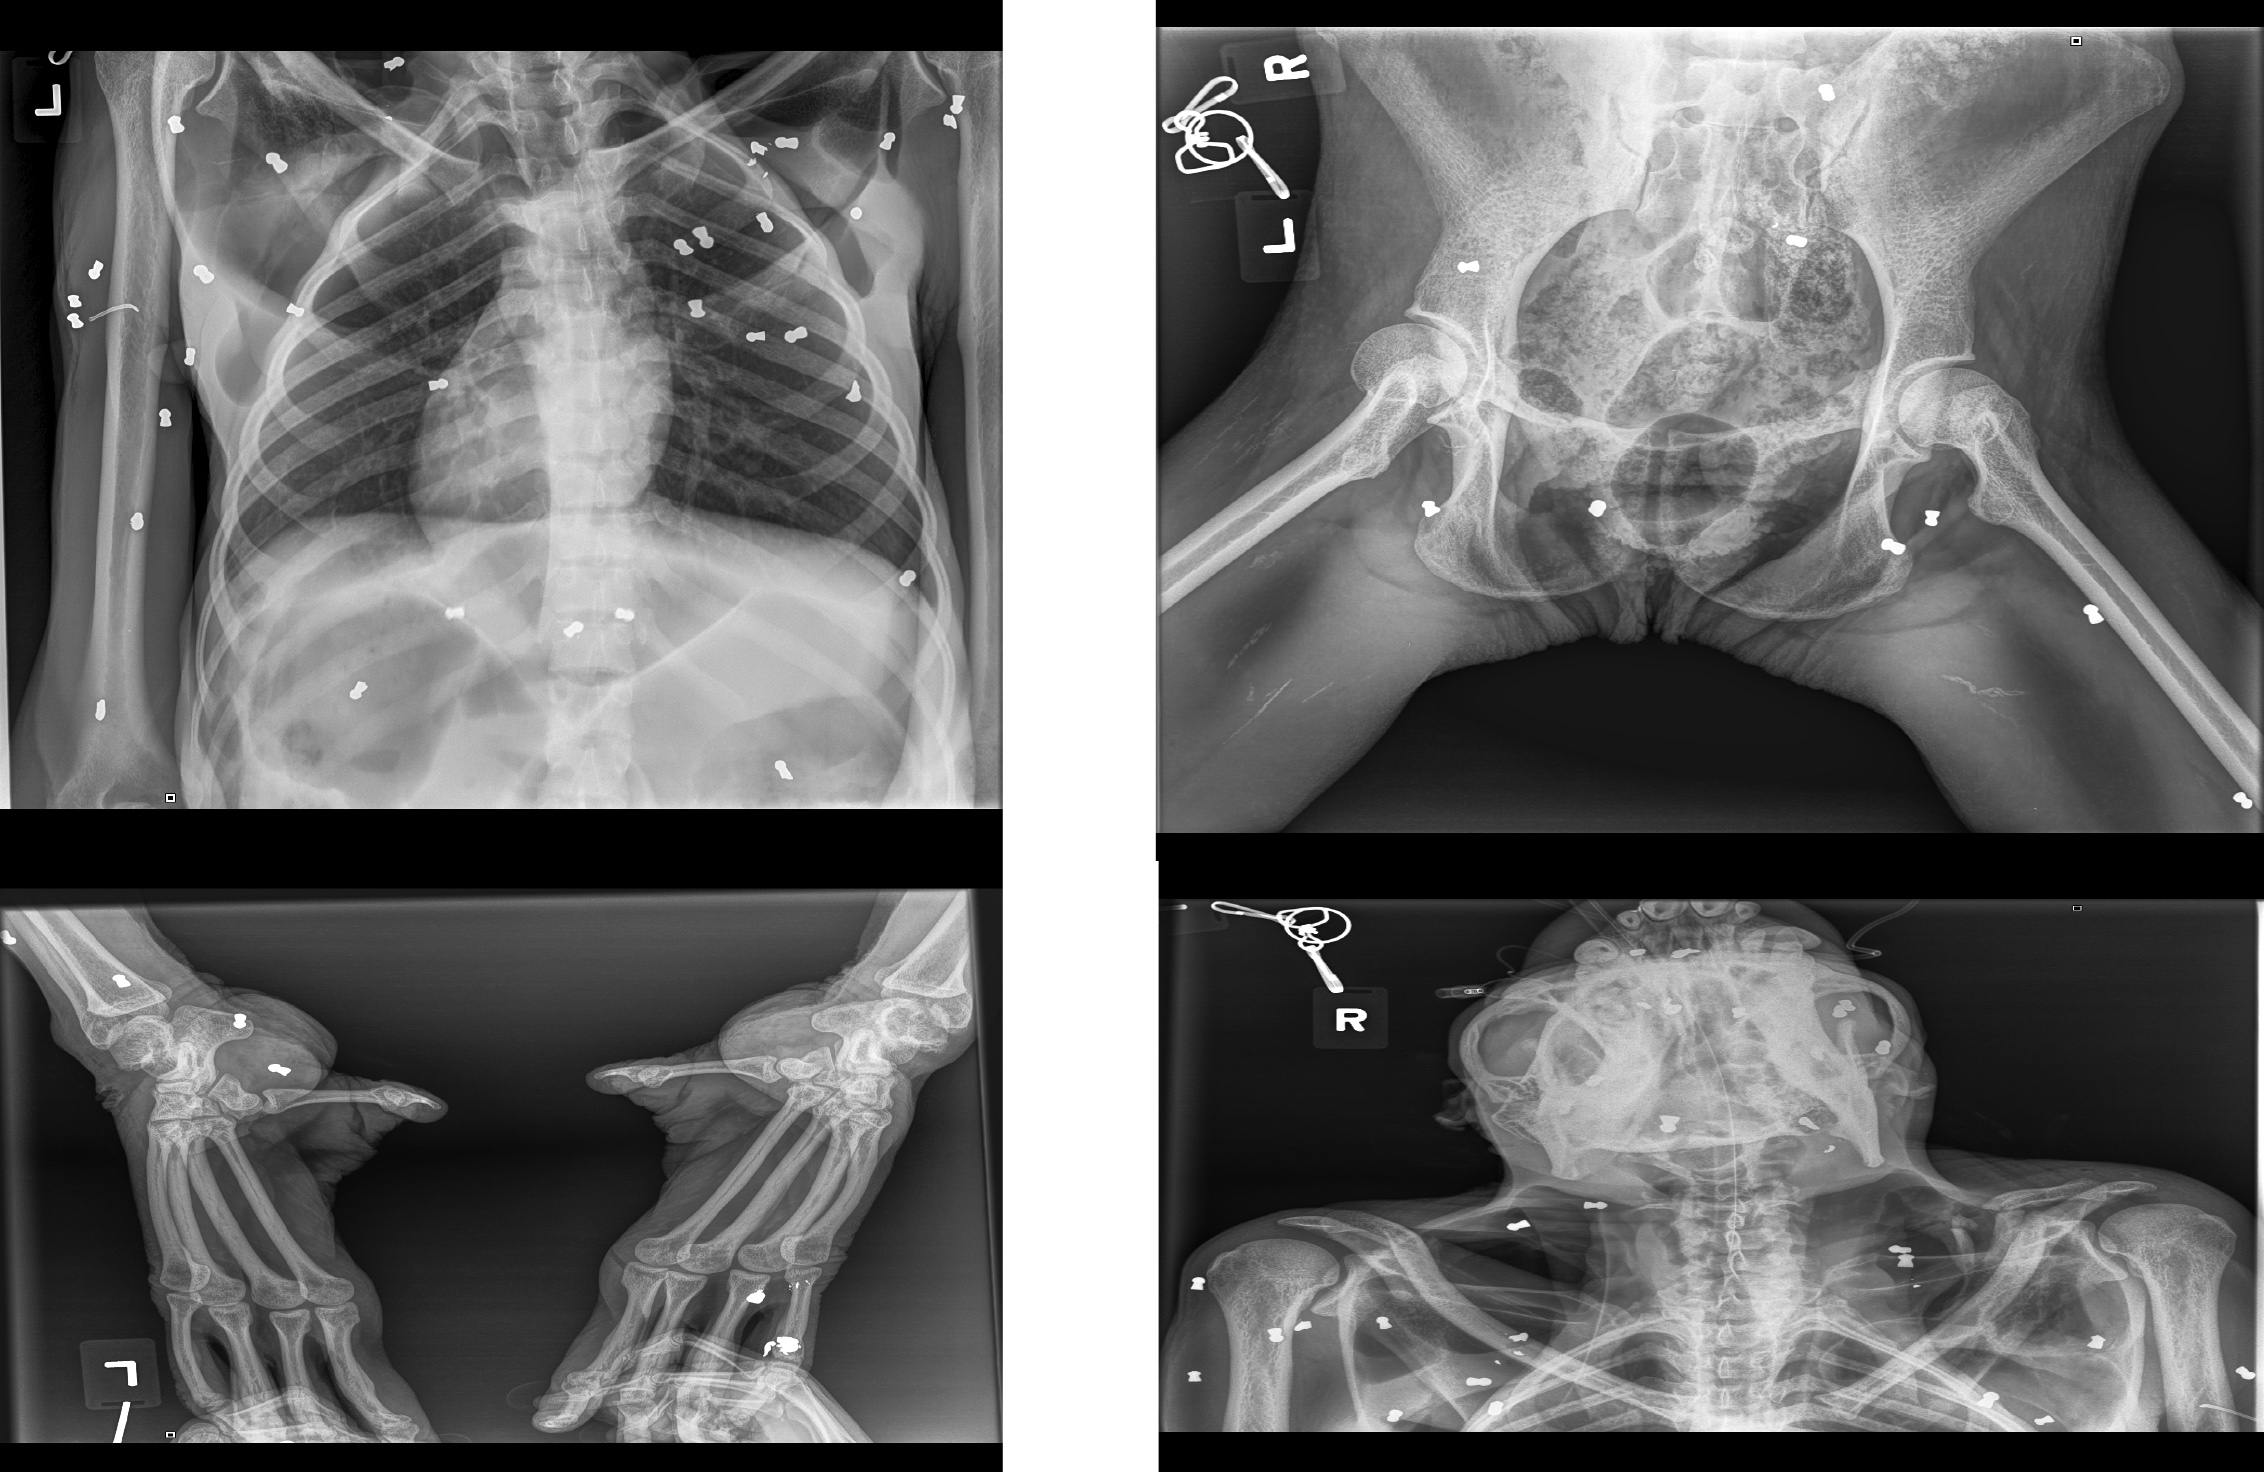

“Hasil x-ray, ditemukan ada sebanyak 74 butir peluru yang tersebar di seluruh badan,” ungkap Kepala BKSDA Aceh Sapto Aji Prabowo, dalam penjelasannya.

Sebutnya, kondisi Hope amat parah saat dievakusi. Pendarahan terjadi di mata kiri bagian kornea dan pupil akibat tiga peluru. Luka lebam di seluruh tubuh, dijumpai di kedua tangan dan ada luka sayatan terbuka di beberapa bagian tubuh.

“Rinciannya, tangan kanan lebar luka 10 cm, tangan kiri luka di bagian jari-jari dengan lebar 2-3 cm. Kaki kanan luka terbuka di bagian paha atas dengan lebar luka 10 cm. Luka terlihat seperti luka sayatan benda tajam, telapak kaki kanan luka terbuka, yang mengakibatkan kerusakan di bagian tendon. Lebar luka 5 cm namun cukup dalam,” ungkap Sapto.

Kaki kiri orangutan itu juga terluka selebar 4 cm dengan kedalaman 1 cm di daerah ruas jari telunjuk. Luka juga dijumpai di bahu kiri dengan lebar luka 1 cm yang cukup dalam, lebih dari 10 cm dan mengenai tulang.